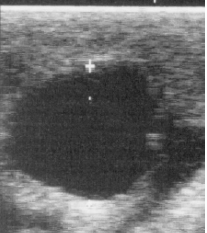

What is an ovarian abnormality?

granulosa cell tumour

<p>granulosa cell tumour</p>